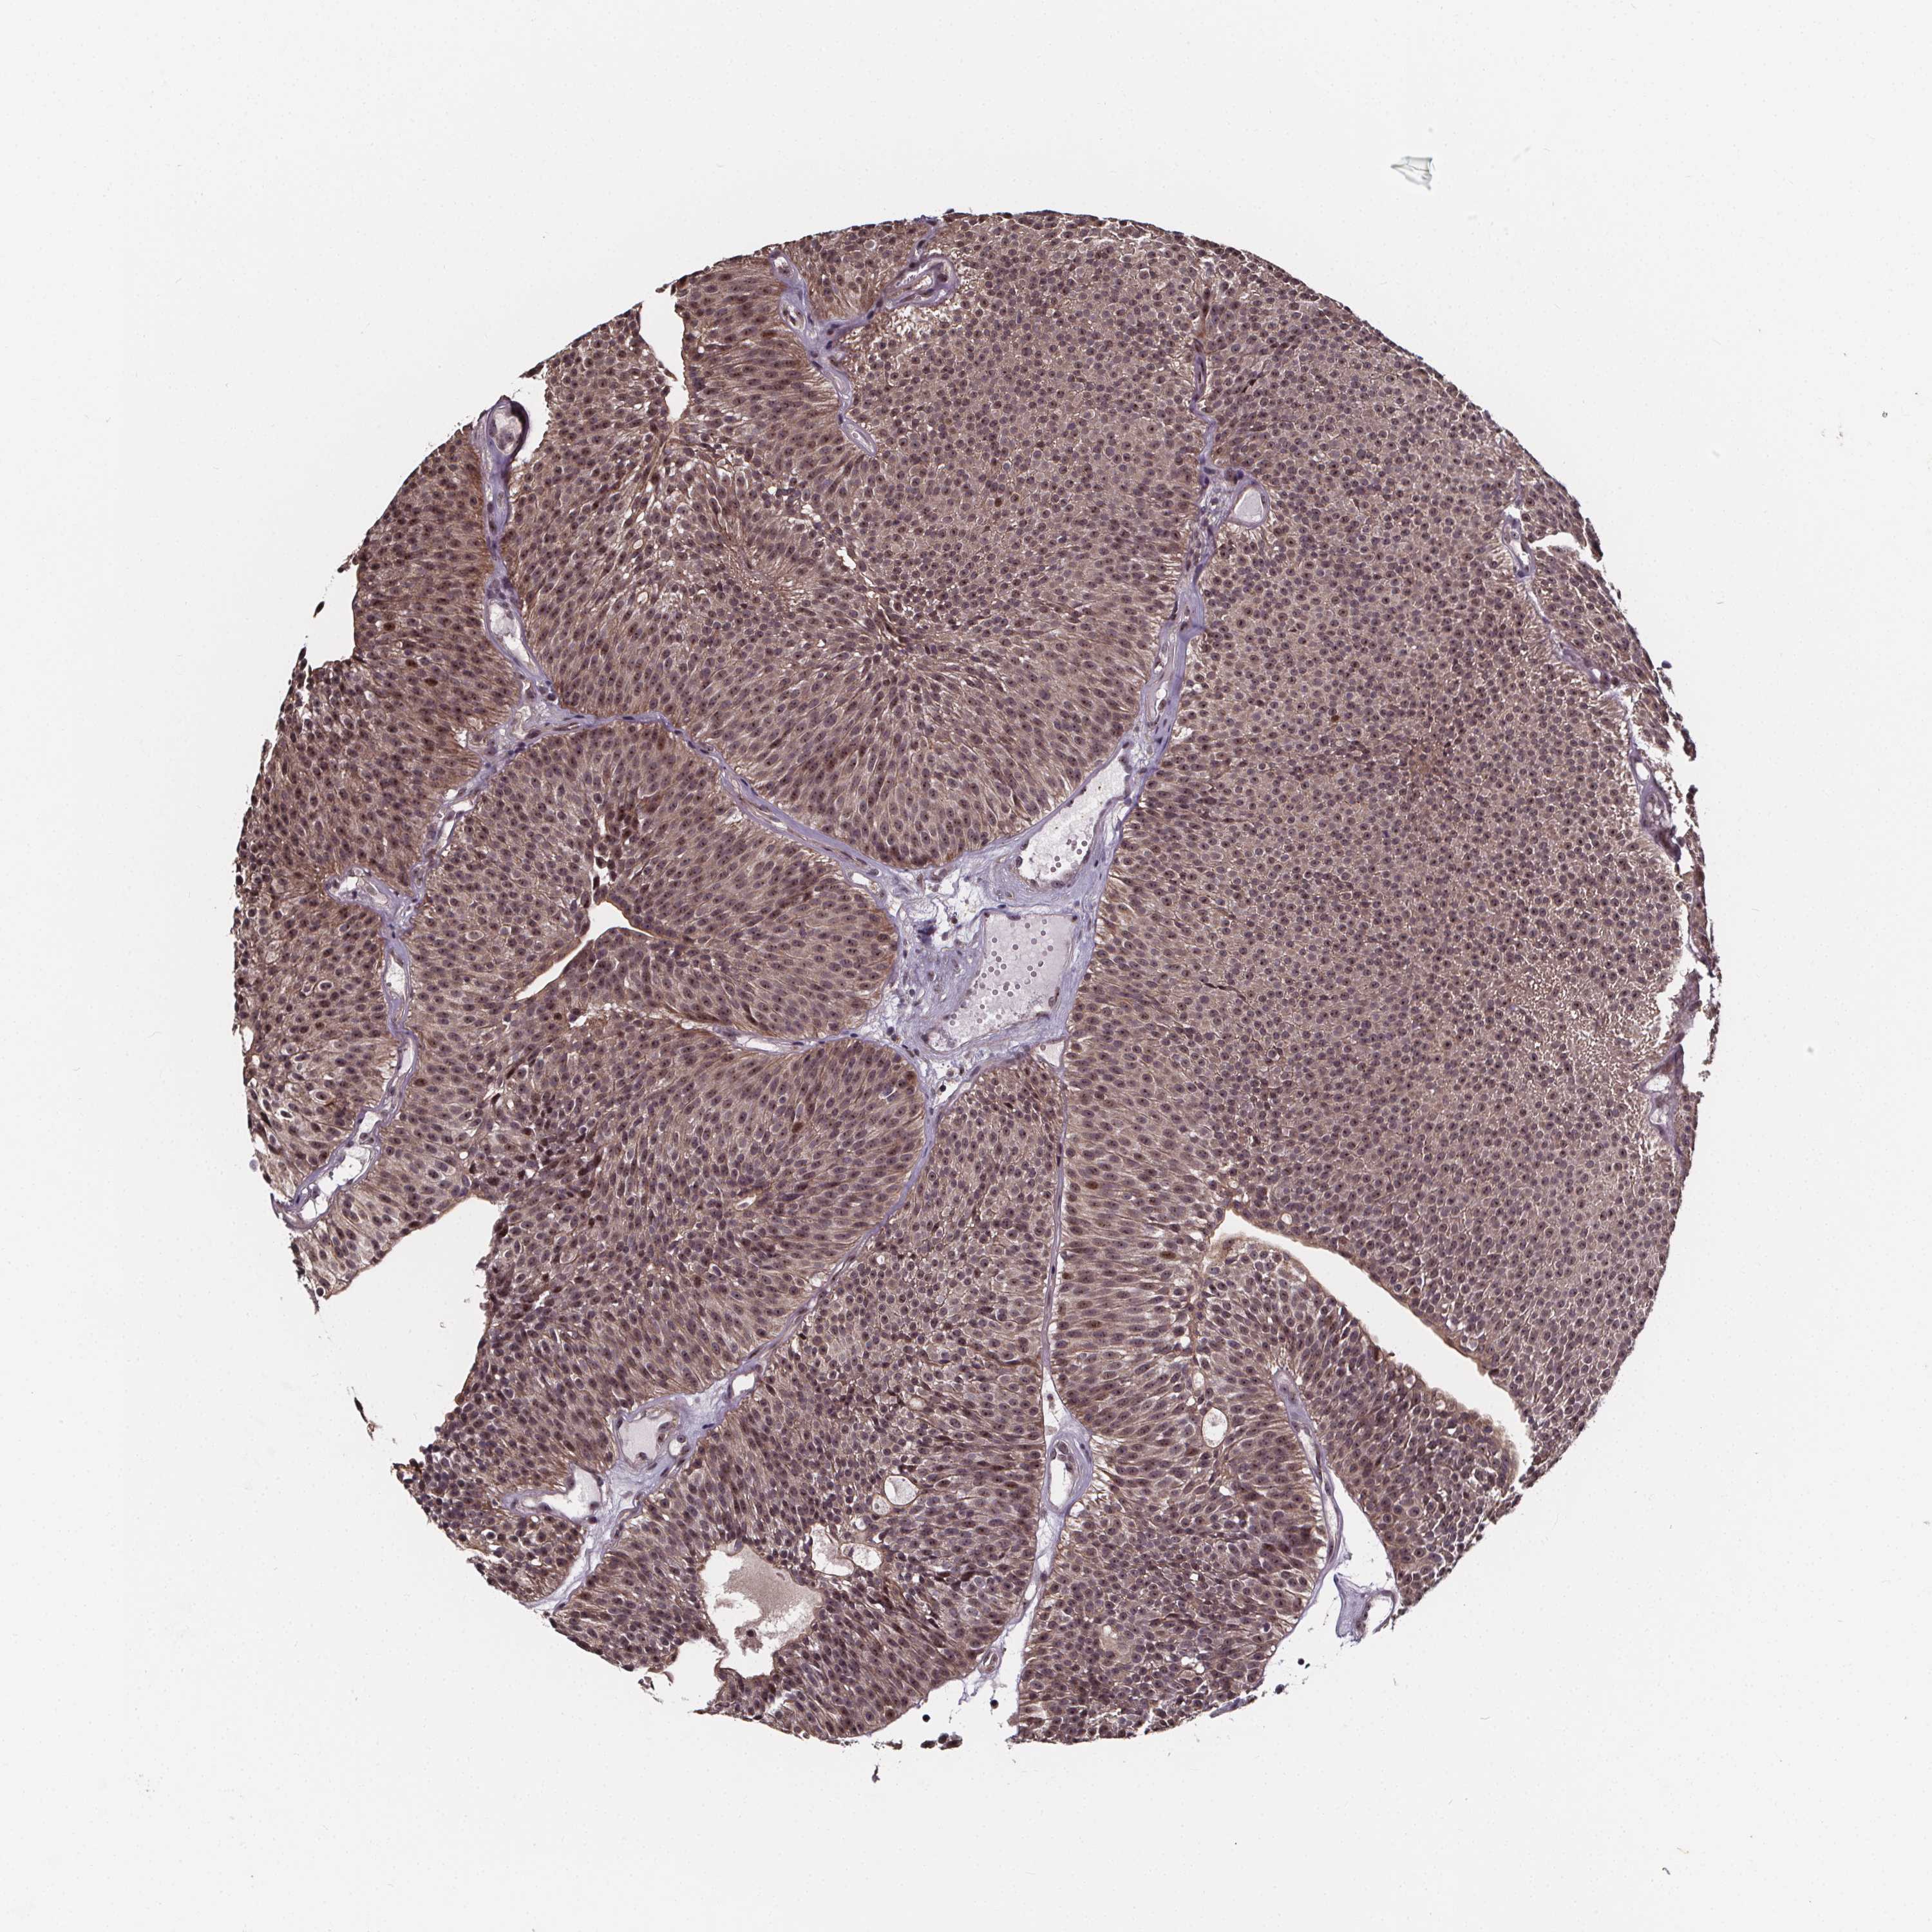

UROTHELIAL CANCER - Protein expressioni

A mouse-over function shows sample information and annotation data. Click on an image to view it in a full screen mode. Samples can be filtered based on level of antibody staining by selecting one or several of the following categories: high, medium, low and not detected. The assay and annotation is described here.

Note that samples used for immunohistochemistry by the Human Protein Atlas do not correspond to samples in the TCGA dataset.

Antibody stainingi

Antibody staining in the annotated cell types in the current human tissue is reported as not detected, low, medium, or high, based on conventional immunohistochemistry profiling in selected tissues. This score is based on the combination of the staining intensity and fraction of stained cells.

Each image is clickable and will lead to virtual microscopy that enables deeper exploration of all samples and also displays staining intensity scores, fraction scores and subcellular localization as well as patient and tissue information for each sample.

Antibody HPA068416

Staining

High

Medium

Low

Not detected

Intensity

Strong

Moderate

Weak

Negative

Quantity

>75%

75%-25%

<25%

None

Location

Nuclear

Cytoplasmic/membranous

Cytoplasmic/membranous,nuclear

Urothelial carcinoma, High grade

Urothelial carcinoma, NOS

Urothelial carcinoma, Low grade